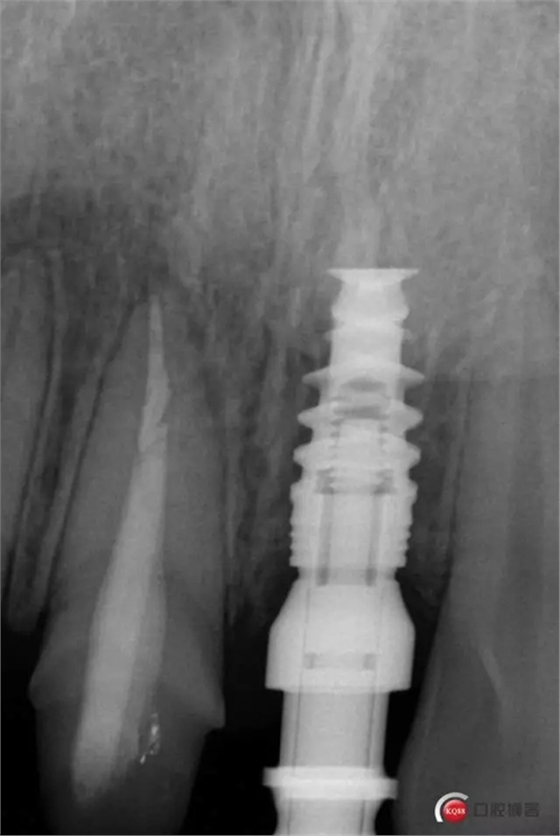

種植后修復,我們要把握每一個細節(jié),比色,轉(zhuǎn)移桿的就位,我們必須把臨床做好,技工師傅才會給我們做出好的修復體,減少一些不必要的失誤,首先術前的檢查是必要一步 ,再是器械的準備使我們臨床操作有條不紊,術前拍照,o-bite取咬合記錄,消毒修復術區(qū),旋出愈合基臺,生理鹽水沖洗袖口,拍照袖口,安放合適轉(zhuǎn)移桿,拍X線見轉(zhuǎn)移桿就為良好,硅橡膠取模,術后旋回愈合基臺,拍照比色。

藻酸鹽對頜取模,超硬石膏灌注。發(fā)加工廠,與技工溝通注意事項,等修復體做好后,檢查模型。是否就位,是否密合,預約患者復診戴牙,消毒修復區(qū),旋出愈合基臺,定位器指導安放修復基臺,試戴冠,調(diào)磨鄰接及 咬合至合適,拋光,患者滿意,加力扳手加力至30N,拍X片見就位良好,特芙蓉及暫封膏封中央螺絲孔,聚羧酸鋅粘固劑粘固,或是樹脂水門汀粘固,清理多余粘結(jié)劑,光固化樹脂封螺絲孔,拋光。術后注意隨訪。